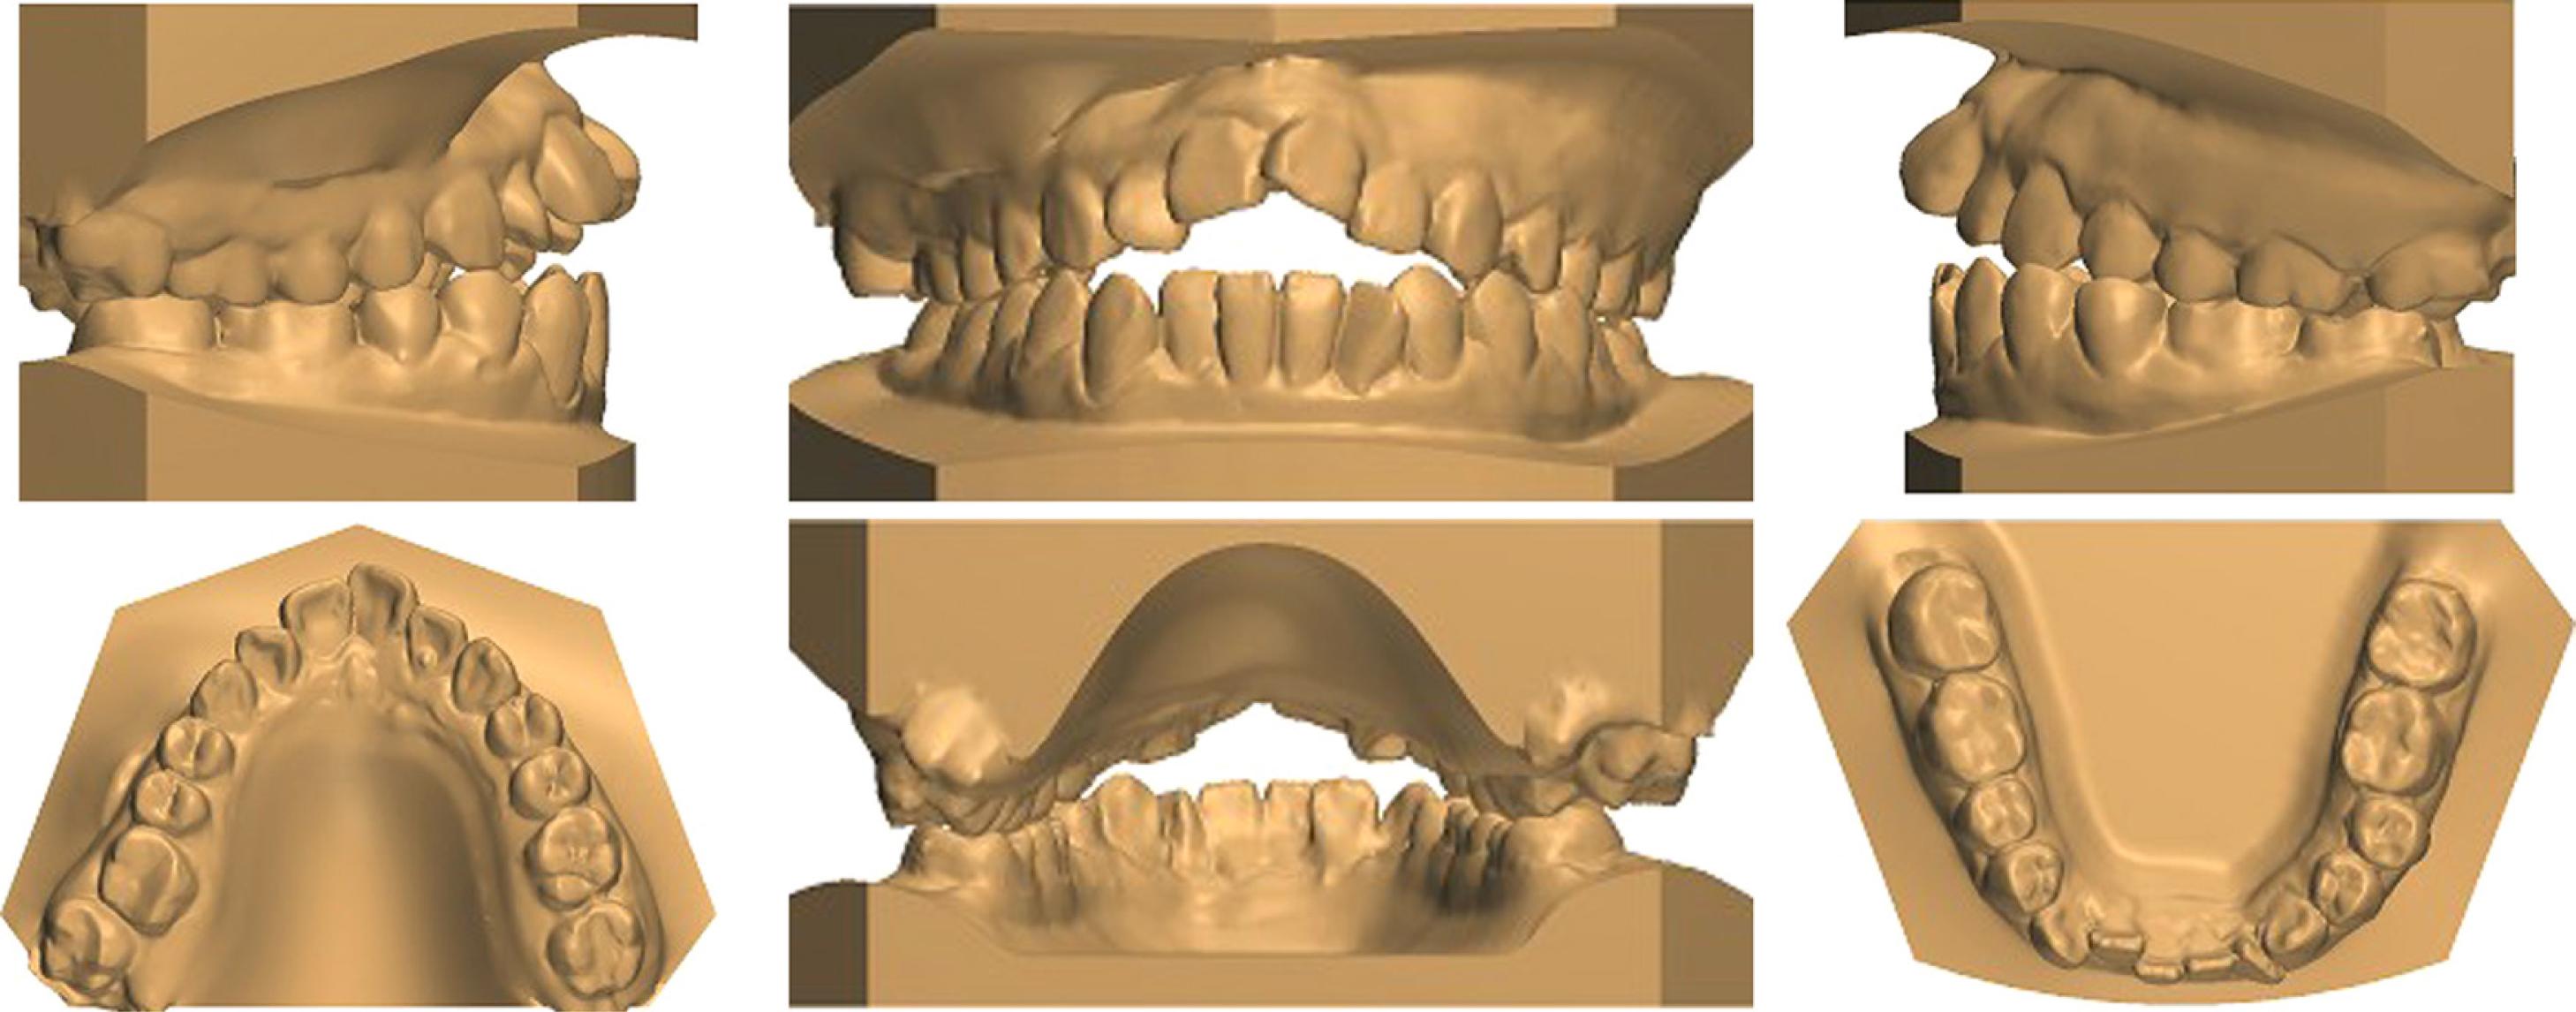

A 24-year-old female patient presented with a history of tongue thrust and mouth breathing but without a history of maxillofacial trauma or a non-nutritive sucking habit. The diagnostic records revealed that, based on the E line, the patient had a convex profile with a long face, a decreased nasolabial angle, a protrusive lower lip, and a shallow mentolabial sulcus. Further, the patient had incompetent and protruded lips at rest and in contact but with mentalis strain upon forcible closure. There was also a low smile line, and the smile arc was not consonant with the curvature of the lower lip (Figure 1). An intraoral examination showed an anterior open bite with no occlusal contact from the right first premolar to the left first premolar, a bilateral Class III molar relationship, and a Class III canine relationship on the right side but a Class I relationship on the left side. An analysis of the initial study models revealed that there was an anterior dental open bite of 6 mm, a decreased overjet (the overjet and overbite were measured on digital dental models using 3-shape software), a 3 mm curve of Spee, a mandibular midline deviation (1.5 mm to the left), and arch-length discrepancies of 5 mm in the maxilla and 3 mm in the mandible. The anterior and overall Bolton ratios were compatible. The maxillary dental arch was narrow, and the upper and lower arches were unmatched. A crossbite from the upper left canine to the second premolar was also noted during the examination. The maxillary right second molar was in scissor-bite with the mandibular right second molar (Figure 2). A cephalometric analysis revealed a skeletal open bite (SN/GO-GN 48°), an increased mandibular plane angle, a counter-clockwise rotation of the ANS-PNS plane (S-N/ANS-PNS 6°), proclination of the upper incisors (UI/ANS-PNS 129°), an interincisal angle of 108°, excessive lower anterior facial height and a short upper anterior facial height (Table I). A computed tomography scan of the anterior teeth revealed adequate labial and lingual bone volumes (Figure 3A). In addition, the initial panoramic radiograph and the radiographic and clinical examinations of the temporomandibular joints revealed no obvious abnormalities (Figure 4 and 3B). The patient was diagnosed with a Class III malocclusion (S-N/ANS-PNS 6°) and skeletal open bite (SN/GO-GN 48°) with an increased mandibular plane angle, a long face, a convex profile, and lip incompetence with mentalis strain. There was also proclination of the upper incisors, a crossbite, scissor-bite, mild crowding and midline deviation.

Initial study models.